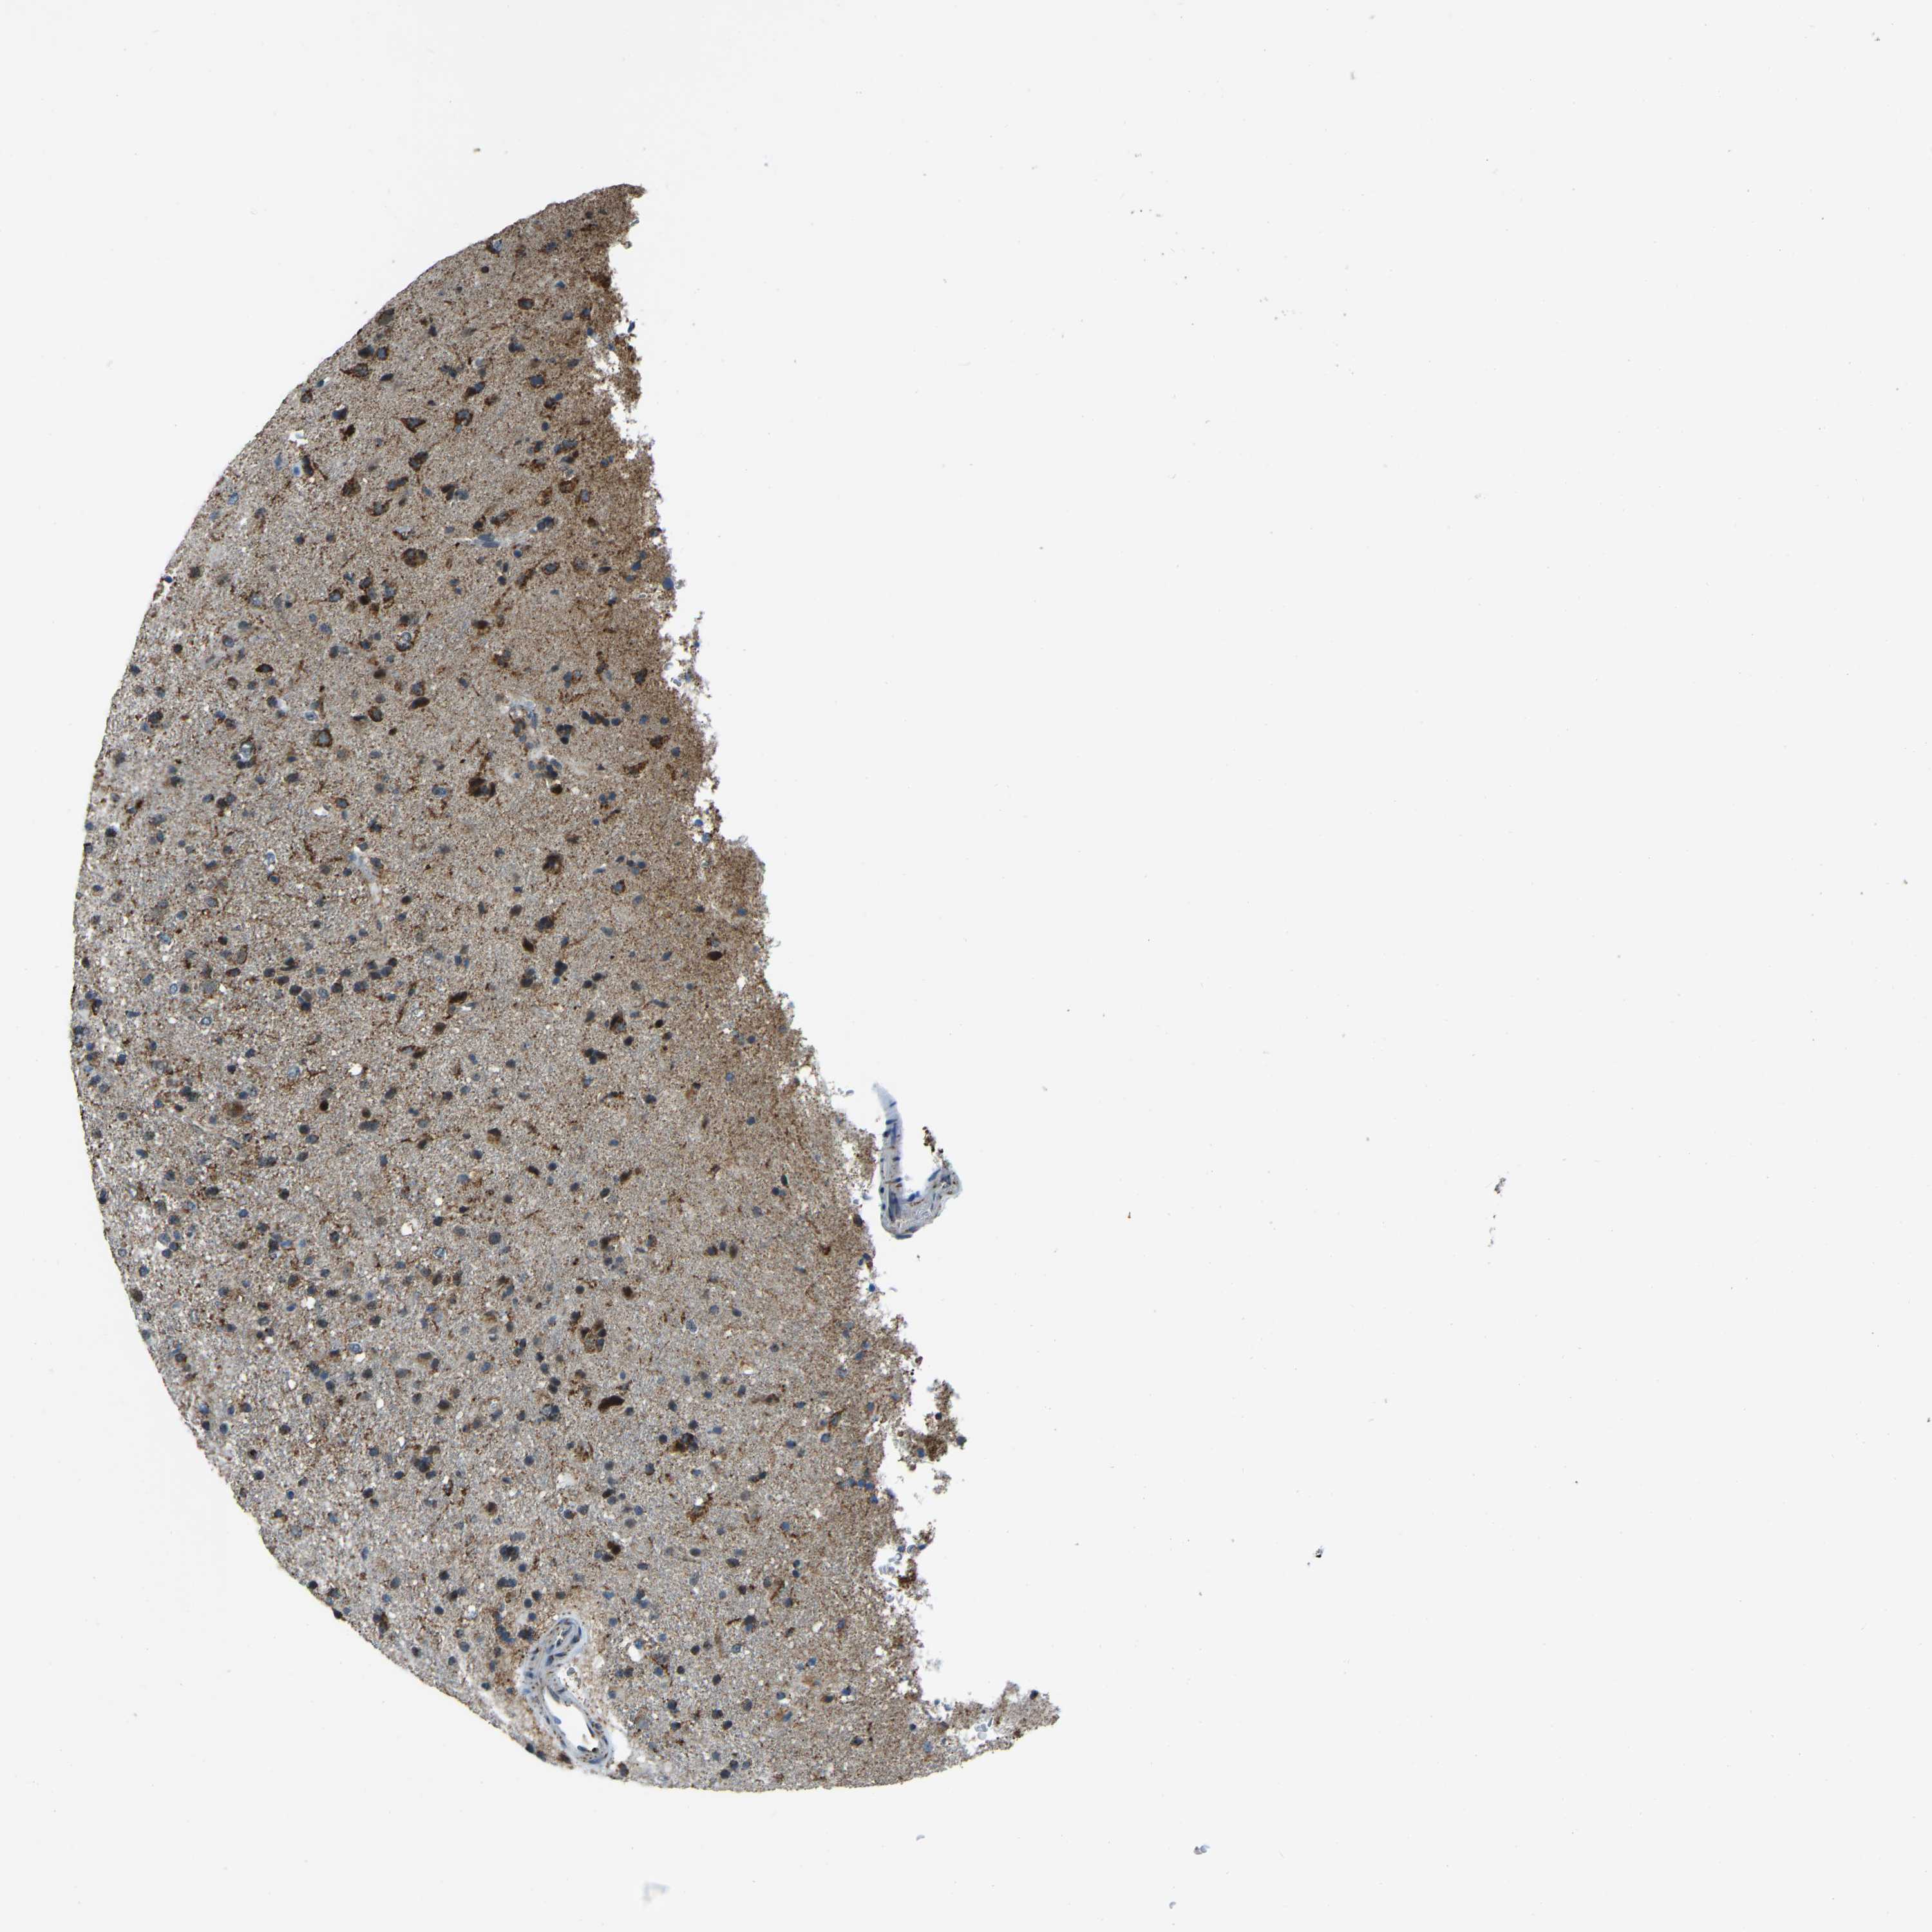

GLIOMA - Protein expressioni

A mouse-over function shows sample information and annotation data. Click on an image to view it in a full screen mode. Samples can be filtered based on level of antibody staining by selecting one or several of the following categories: high, medium, low and not detected. The assay and annotation is described here.

Note that samples used for immunohistochemistry by the Human Protein Atlas do not correspond to samples in the TCGA dataset.

Antibody stainingi

Antibody staining in the annotated cell types in the current human tissue is reported as not detected, low, medium, or high, based on conventional immunohistochemistry profiling in selected tissues. This score is based on the combination of the staining intensity and fraction of stained cells.

Each image is clickable and will lead to virtual microscopy that enables deeper exploration of all samples and also displays staining intensity scores, fraction scores and subcellular localization as well as patient and tissue information for each sample.

Antibody HPA019232

Antibody HPA021497

Antibody HPA021768

Staining

High

Medium

Low

Not detected

Intensity

Strong

Moderate

Weak

Negative

Quantity

>75%

75%-25%

<25%

None

Location

Nuclear

Cytoplasmic/membranous

Cytoplasmic/membranous,nuclear

Glioma, malignant, High grade

Glioma, malignant, Low grade